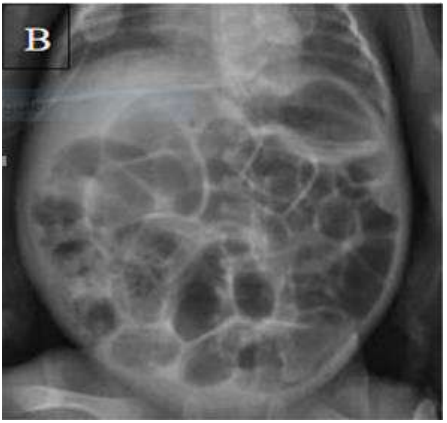

Uma recém-nascida (RN) pré-termo, com 28 semanas de idade gestacional, aos seis dias de vida, inicia quadro de instabilidade térmica, hipoatividade, apneia, resíduo gástrico aumentado, diminuição da perfusão periférica, distensão abdominal, ausência dos ruídos hidroaéreos e enterorragia. Verificam-se SatO2 = 92%, FC = 120 bpm e FR = 65 irpm. Ela é filha de pais saudáveis, não consanguíneos, com sorologias maternas sem alterações. O parto ocorreu por cesariana, com um índice de Apgar ao 1º e 5ºminuto de 7 e 8 respectivamente (PN = 1.055 g; comp = 36 cm; PC = 28,5 cm). Teve a primeira eliminação de mecônio nas primeiras 24 horas de vida. O resultado de exames laboratoriais evidenciou leucopenia, neutropenia, queda aguda do hematócrito e trombocitopenia. A imagem do exame radiológico encontra-se a seguir.

Acerca desse caso clínico e considerando os conhecimentos médicos correlatos, julgue os itens a seguir.

Faz parte do tratamento da patologia, nesse estágio, a nutrição por sonda, pois a parenteral pode culminar com necrose das alças intestinais afetadas, permitindo a passagem de bactérias e toxinas para a circulação sistêmica.